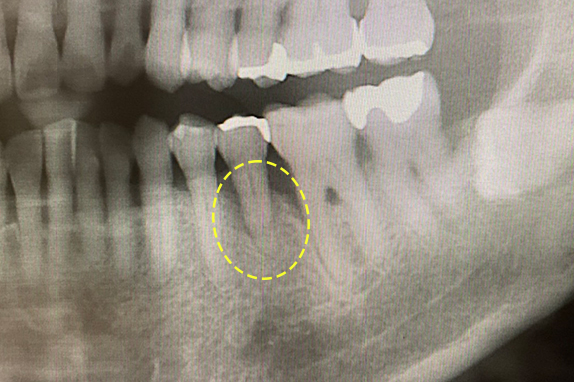

CASE 01 歯周再生治療

-

- 主訴

- 歯がグラグラで噛めない

-

- 回数期間

- 5回 約1年

-

- 治療法

- 歯周再生治療

-

- 治療費用

- 約17万円(税抜)

歯がグラグラで噛めないという主訴の患者様に歯周再生治療を用いて改善したケースです。レントゲン写真をみると術前は歯肉の退縮が見られるが、術後は歯肉の退縮が改善しています。

<リスク・副作用>

手術後は腫れ、痛み、痺れなどの副作用が生じる場合があります。